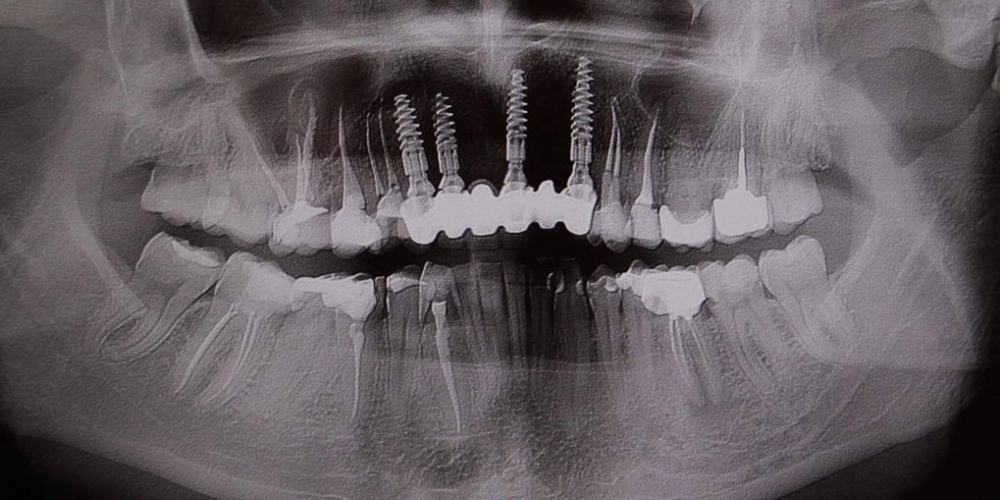

Дентальные снимки и диагностика кариеса